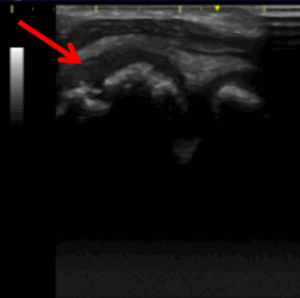

・超音波検査:肘周囲の靱帯、成長軟骨、遊離体の状態を診察室で検査